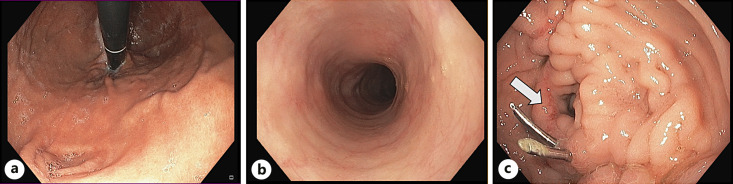

Background: Sinistral, or left-sided, portal hypertension (SPH) is a rare cause of upper gastrointestinal (GI) hemorrhage resulting from obstruction of the splenic vein. Venous drainage from the spleen via collaterals can result in venous hemorrhage into both the retroperitoneal and intra-abdominal spaces due to increased venous blood pressure in peripancreatic and gastroduodenal vasculature. SPH can occur secondary to pancreatitis with thrombosis of the splenic vein. Another possible cause is the surgical ligation of the splenic vein as part of pancreaticoduodenectomy (PD). Although splenectomy has been traditionally considered as the treatment of choice to relieve venous hypertension, individual concepts for each patient have to be developed. Considering the venous collateral drainage pathways, a comprehensive approach involving surgical, endoscopic, and interventional radiology interventions may be necessary to address the underlying cause of variceal bleeding. Among these approaches, splenic artery embolization (SAE) has demonstrated efficacy in mitigating the adverse effects associated with elevated venous outflow pressure.

Summary: This review summarizes key imaging findings in SPH patients after PD and highlights the potential of minimally invasive embolization for curative treatment of variceal hemorrhage.

Key messages: (i) SPH is a potential consequence after major pancreas surgery. (ii) Collateral flow can lead to life-threatening abdominal bleeding. (iii) Depending on the origin and localization of the bleeding, a dedicated management is required, frequently involving interventional radiology techniques.